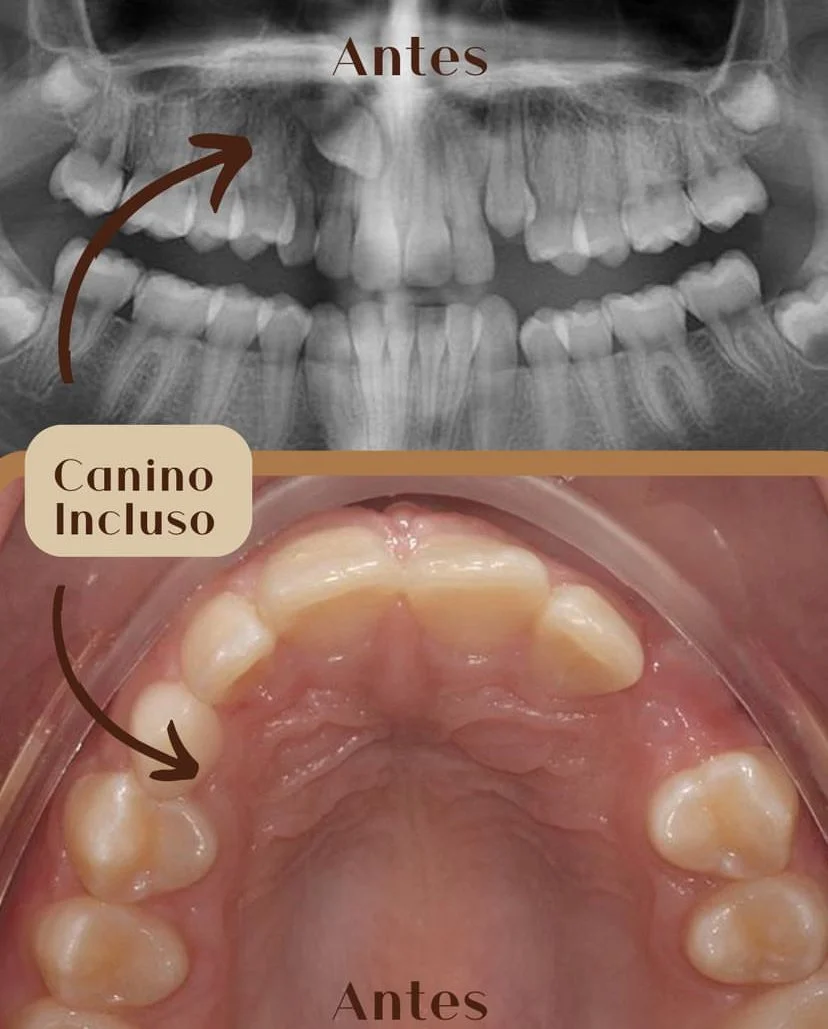

Cirurgia oral

Ortodontia